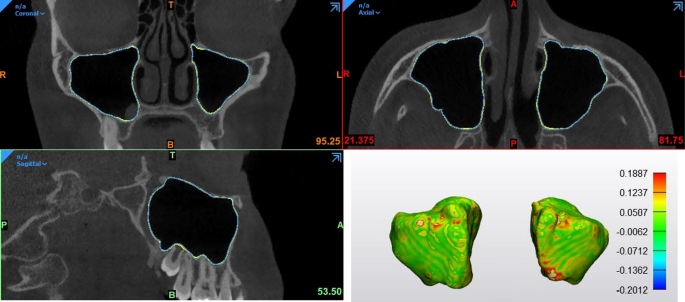

Table 3 provides an overview of the accuracy metrics for automatic segmentation. Overall, the automatic segmentation showed a DSC of 98.4% and RMS of 0.21 mm in comparison to the ground truth, implying that the 3D volumes and models along with the surfaces were closely matched between them. (Fig. 4).

The comparison between automatic and refined segmentations showed a DSC of 99.6% and RMS of 0.21 mm indicating perfect overlap between them. The minimal difference meant that minor refinements were needed.